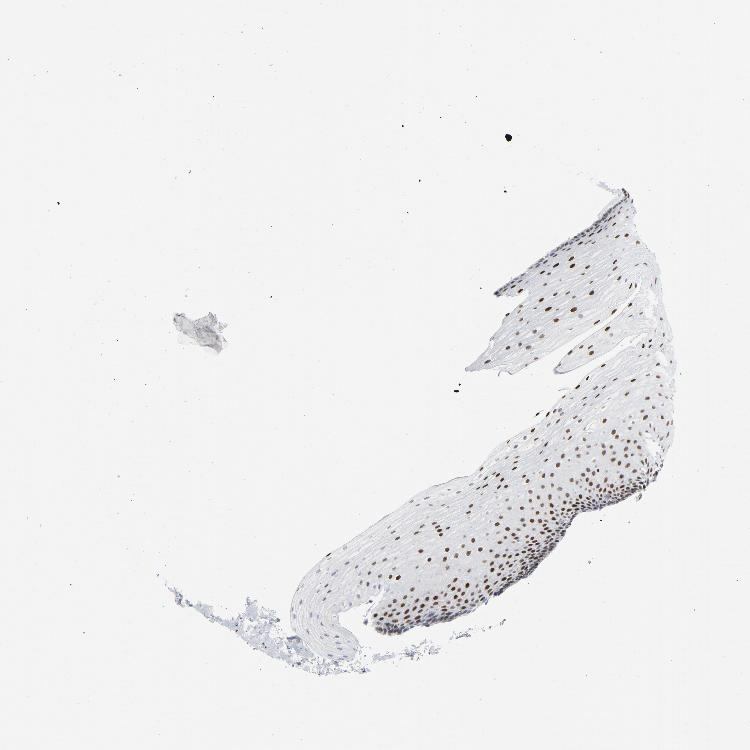

ESOPHAGUS - Antibody stainingi

Antibody staining in the annotated cell types in the current human tissue is reported as not detected, low, medium, or high, based on conventional immunohistochemistry profiling in selected tissues. This score is based on the combination of the staining intensity and fraction of stained cells.

Each image is clickable and will lead to virtual microscopy that enables deeper exploration of all samples and also displays staining intensity scores, fraction scores and subcellular localization as well as patient and tissue information for each sample.

Antibody HPA008888Antibody CAB004239

Squamous epithelial cells HighHigh